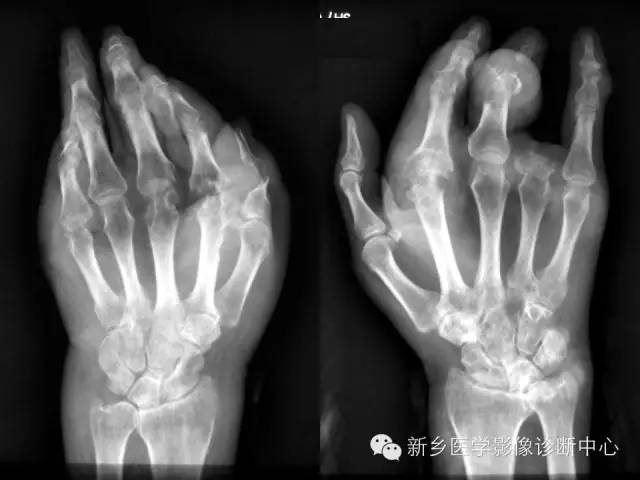

痛风1例X线影像表现